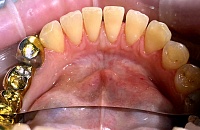

Работы врача